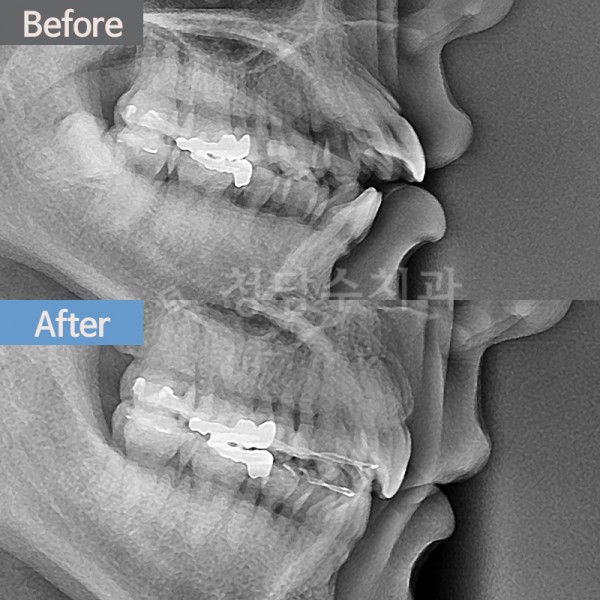

치아교정 돌출입교정

돌출입교정